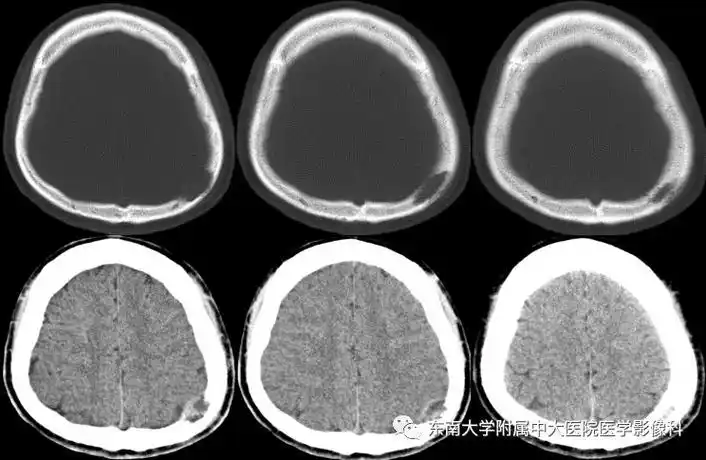

颅骨骨瘤

颅骨良性肿瘤的影像诊断

骨瘤